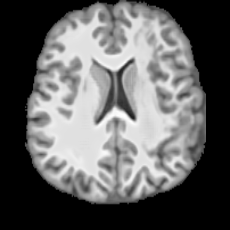

Healthy w/Lesion MaskPathologicalDifferencew/o LCGw/ LCG(a)Refer to captionRefer to captionRefer to captionRefer to captionRefer to captionRefer to captionHealthy w/Lesion MaskPathologicalDifferencew/o LCGw/ LCG(b)Refer to captionRefer to captionRefer to captionRefer to captionRefer to captionRefer to caption

Figure 7: Ablation study of Lesion Consistency Guidance (LCG). Without LCG, the generated pathological regions are indistinct and show weak pathological expression in both examples.

Lesion Consistency Guidance. Fig. 7 illustrates the impact of Lesion Consistency Guidance (LCG) for healthy-to-pathology editing. Without LCG, the generated lesion regions appear blurry around lesion boundaries, and the pathological patterns are less distinct, resulting in ambiguous lesion localization and weak pathological expression. Incorporating LCG produces lesions with more precise localization and well-defined shapes that better align with the given lesion masks, as well as textures and contrasts that exhibit stronger pathological characteristics. These results demonstrate that LCG effectively enforces lesion-aware conditioning, enhancing both spatial and semantic consistency of the generated pathological regions.